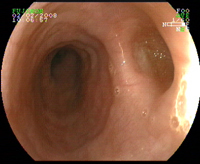

Q

Coloscopie pour bilan d’anémie ferriprive. qu’est ce que c’est?

A

tumeur colique